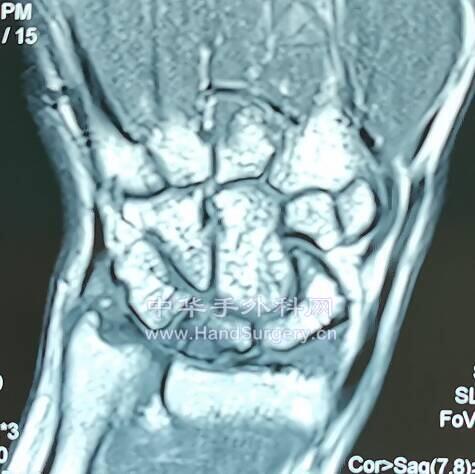

月骨坏死分型:

微信截图_20200620170155.png

月骨坏死III期

微信截图_20200620170439.png

微信截图_20200620170520.png

微信截图_20200620170555.png